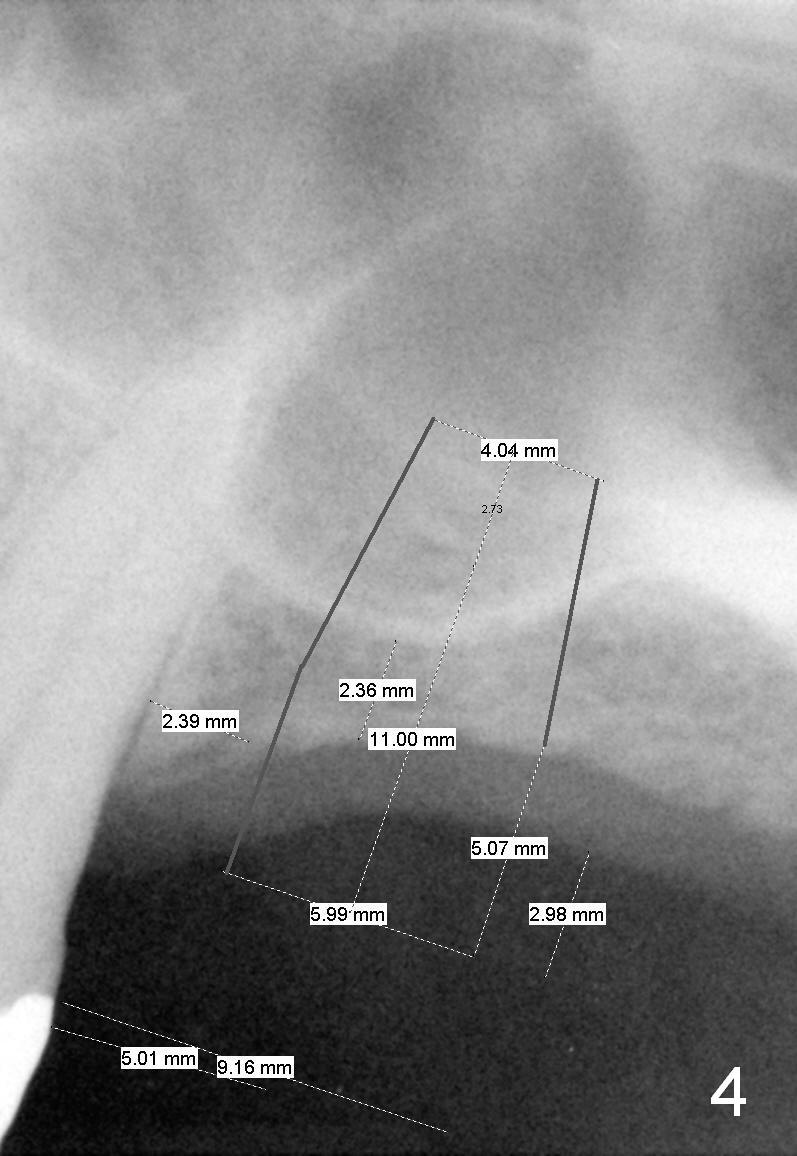

A 60-year-old man requests implant at the site of #14 (Fig.1,2, opposing a natural tooth (Fig.7)). Although bone height is limited, bone density appears high with sinus septi (S and arrowheads). The ridge seems to be wide clinically; implant will be as wide as possible. An envelop incision will be made to get the best visibility (as compared to tissue punch). At entry point, the bone height is 2.5 mm (Fig.3 red line); as the implant or osteotomy diameter increases, bone contact enhances (pink lines). If lateral window approach is adopted, a longer implant will be chosen (14 mm in Fig.3 vs. 11 mm in Fig.4, both tissue-level). The stronger distal septum may deviate the apical portion of the longer implant (Fig.3 arrow).

Another set of choice will be bone-level implants (SM and UF). The advantage of the former is its taper; the difference of the base and apex diameter is 1.1 mm (Fig.5 vs. 0.6 mm for UF (Fig.6)). It appears that a smaller parallel-walled drills can be used for the former (underprep) so that primary stability is more easily achievable. But according to the manufacture, the design of the latter allows the threads to be more aggressive. The surface treatment of the latter is more advanced (hybrid sand blast & acid etched vs. resorbable blast media; osseointegration occurs quicker for the latter). Which implant is finally chosen?